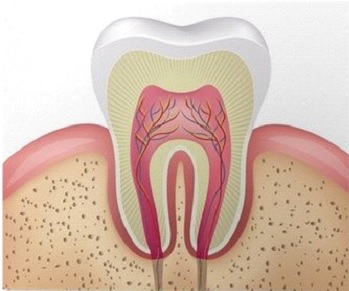

Anatomia przyzębia. Tkanki otaczające ząb i utrzymujące go w kości nazywamy przyzębiem. Podstawę kostną tworzy kość gąbczasta i pokrywająca ją kość korowa wyrostka zębodołowego. Organizm wytwarza kość wyrostka zębodołowego w procesie wyrzynania się zębów, w tym samym procesie dochodzi również do formowania się tkanek przyzębia. Pomiędzy cementem (tkanka pokrywającą korzeń zęba) oraz blaszką kostną zębodołu rozpięte są dziesiątki tysięcy włókien ozębnowych. Na powierzchni kości, wokół zębów znajduje się tkanka dziąsła, którą dzielimy na dziąsło przytwierdzone, które jest zrośnięte z okostną oraz dziąsło ruchome otaczające zęby charakterystyczną girlandą i tworzące w przestrzeniach międzyzębowych brodawki dziąsłowe. Różowe trójkąciki brodawek dziąsłowych szczelnie wypełniają podcienie poniżej punktów, gdzie stykają się ze sobą korony zębów.

Dziąsło łączy się z powierzchnią zęba tkanką, którą nazywamy przyczepami dziąsłowymi. Od strony korony zęba, sąsiaduje z jamą ustną przyczep nabłonkowy, poniżej którego jest przyczep łącznotkankowy. Oba przyczepy tworzą funkcjonalną całość i wzajemnie się uzupełniają swoimi właściwościami. Na powierzchni dziąsła jest nabłonek wielowarstwowy, płaski, rogowaciejący który jest zrośnięty z okostną. Około 70% objętości dziąsła tworzą włókna kolagenowe. Budowa histologiczna dziąsła oraz prawidłowe ukształtowanie łuków zębowych gwarantuje dużą wytrzymałość mechaniczną, termiczną, chemiczną oraz biologiczną odporność na działanie flory bakteryjnej.

Rysunek przedstawiający zdrowe przyzębie.

Tkanka dziąsła otaczająca zęby w stanie zdrowym jest bladoróżowa, jędrna i sprężysta. Pas tkanki dziąsła może być grubszy i szerszy, albo cieńszy i węższy, dzieli się na dziąsło przytwierdzone, oraz dziąsło wolne. W miejscu, gdzie dziąsło brzeżne dotyka zęba znajduje się wejście do szczeliny dziąsłowej. Szczelina dziąsłowa w zdrowych tkankach nie przekracza głębokości 3 mm. Jeżeli przekracza 3 mm to mówimy już o kieszonce dziąsłowej. Na dnie szczeliny (kieszonki dziąsłowej) tkanki dziąsła przyrastają do zęba przyczepami dziąsłowymi. Szerokość zdrowego przyczepu dziąsłowego wynosi około 2 mm. Na dnie szczeliny dziąsłowej powstaje płyn dziąsłowy, który pomaga w oczyszczaniu kieszonki i utrzymaniu tkanek dziąsła brzeżnego w stanie zdrowia. Wzrost wypływu płynu dziąsłowego, któremu towarzyszy tendencja do krwawienia – to są pierwsze objawy zapalenia dziąsła.